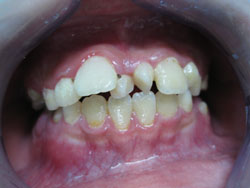

- *Răng mọc chen chúc:

- Răng mọc chen chúc là tình trạng các răng sắp xếp lộn xộn, không ngay ngắn trên cung hàm , răng mọc không đều, các răng khấp khểnh do thiếu chỗ (răng quá to hay xương hàm cung răng quá nhỏ không đủ chỗ để các răng sắp xếp).